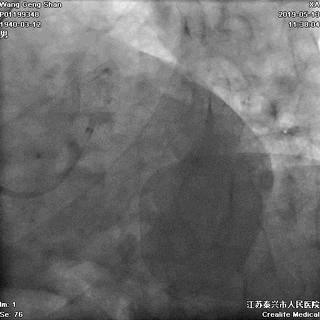

LCX球囊拘禁,主支支架释放

回撤LCX球囊

支架球囊再次扩张支架